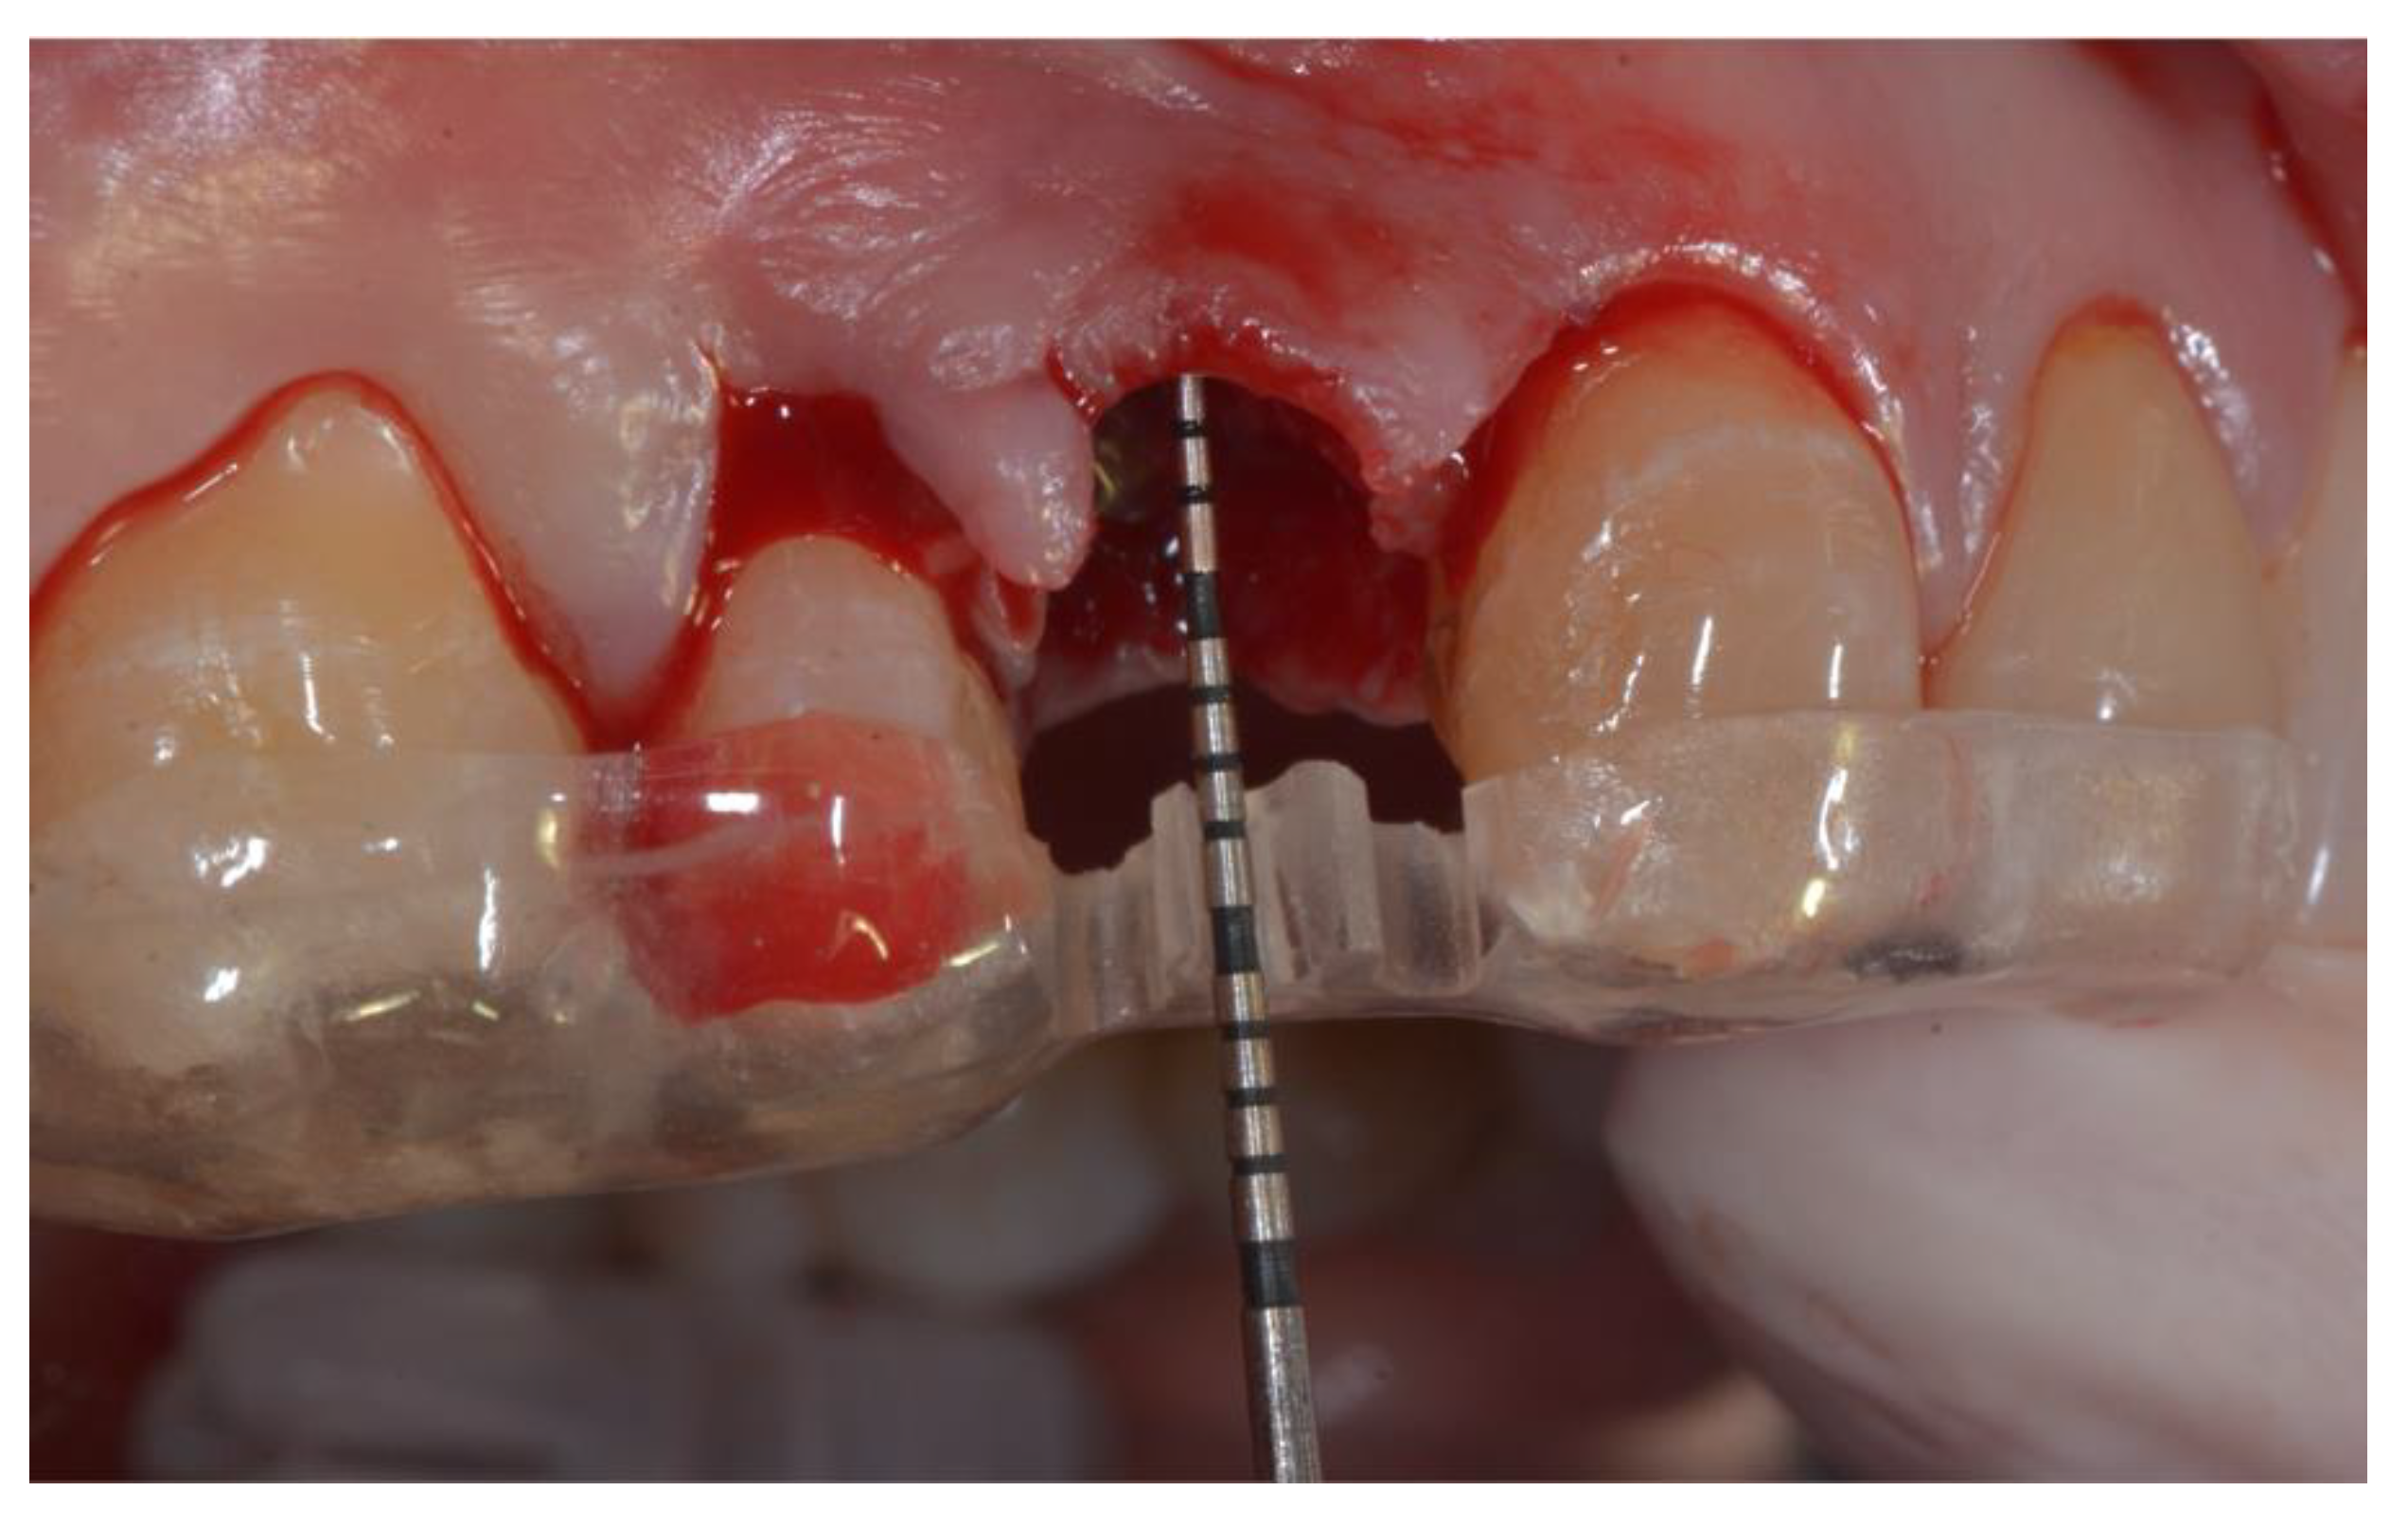

All patients rinsed for one minute with chlorhexidine mouthwash 0.2% before the surgery (and two times a day for the following three weeks). Under local anesthesia using lidocaine (adrenaline 1:50,000), patients were operated with the same surgical approach consisting of minimally invasive tooth extraction, without raising a muco-periosteal flap. Great attention was taken to reduce the damage to the vestibular bone plate and to maintain the integrity of the alveolar bone morphology. The extraction sockets were thoroughly debrided to remove all soft tissue, subsequently, the acrylic custom-made template was used to take the horizontal and vertical bone measurements. The surgical template was stabilized on the adjacent teeth to allow reproducible horizontal and vertical measurements at the different time points of the study. The vertical measurements were performed taking the surgical stent as reference point, as shown in

Figure 1.